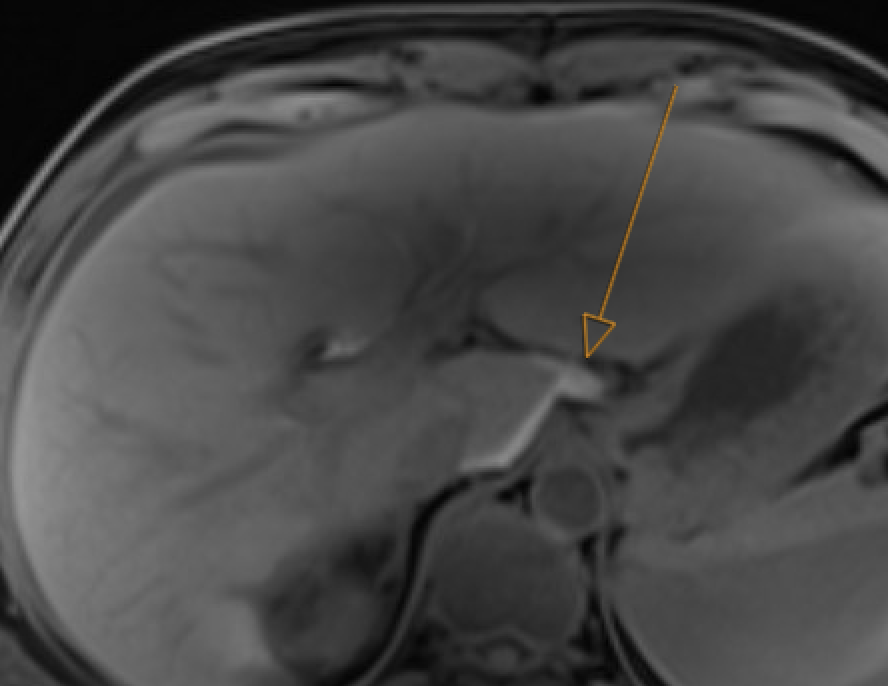

Gangrenous cholecystitis Focal GB wall nonenhancement or discontinuity; intramural abscess (rim-enhancing + diffusion-restricting collection); contained perforation

MRI showing focal gallbladder wall nonenhancement consistent with gangrenous/necrotizing cholecystitis

Gangrenous cholecystitis: focal wall nonenhancement

Abscess: rim enhancement + central DWI restriction. Hematoma: central DWI restriction but no rim enhancement + T1 hyperintensity